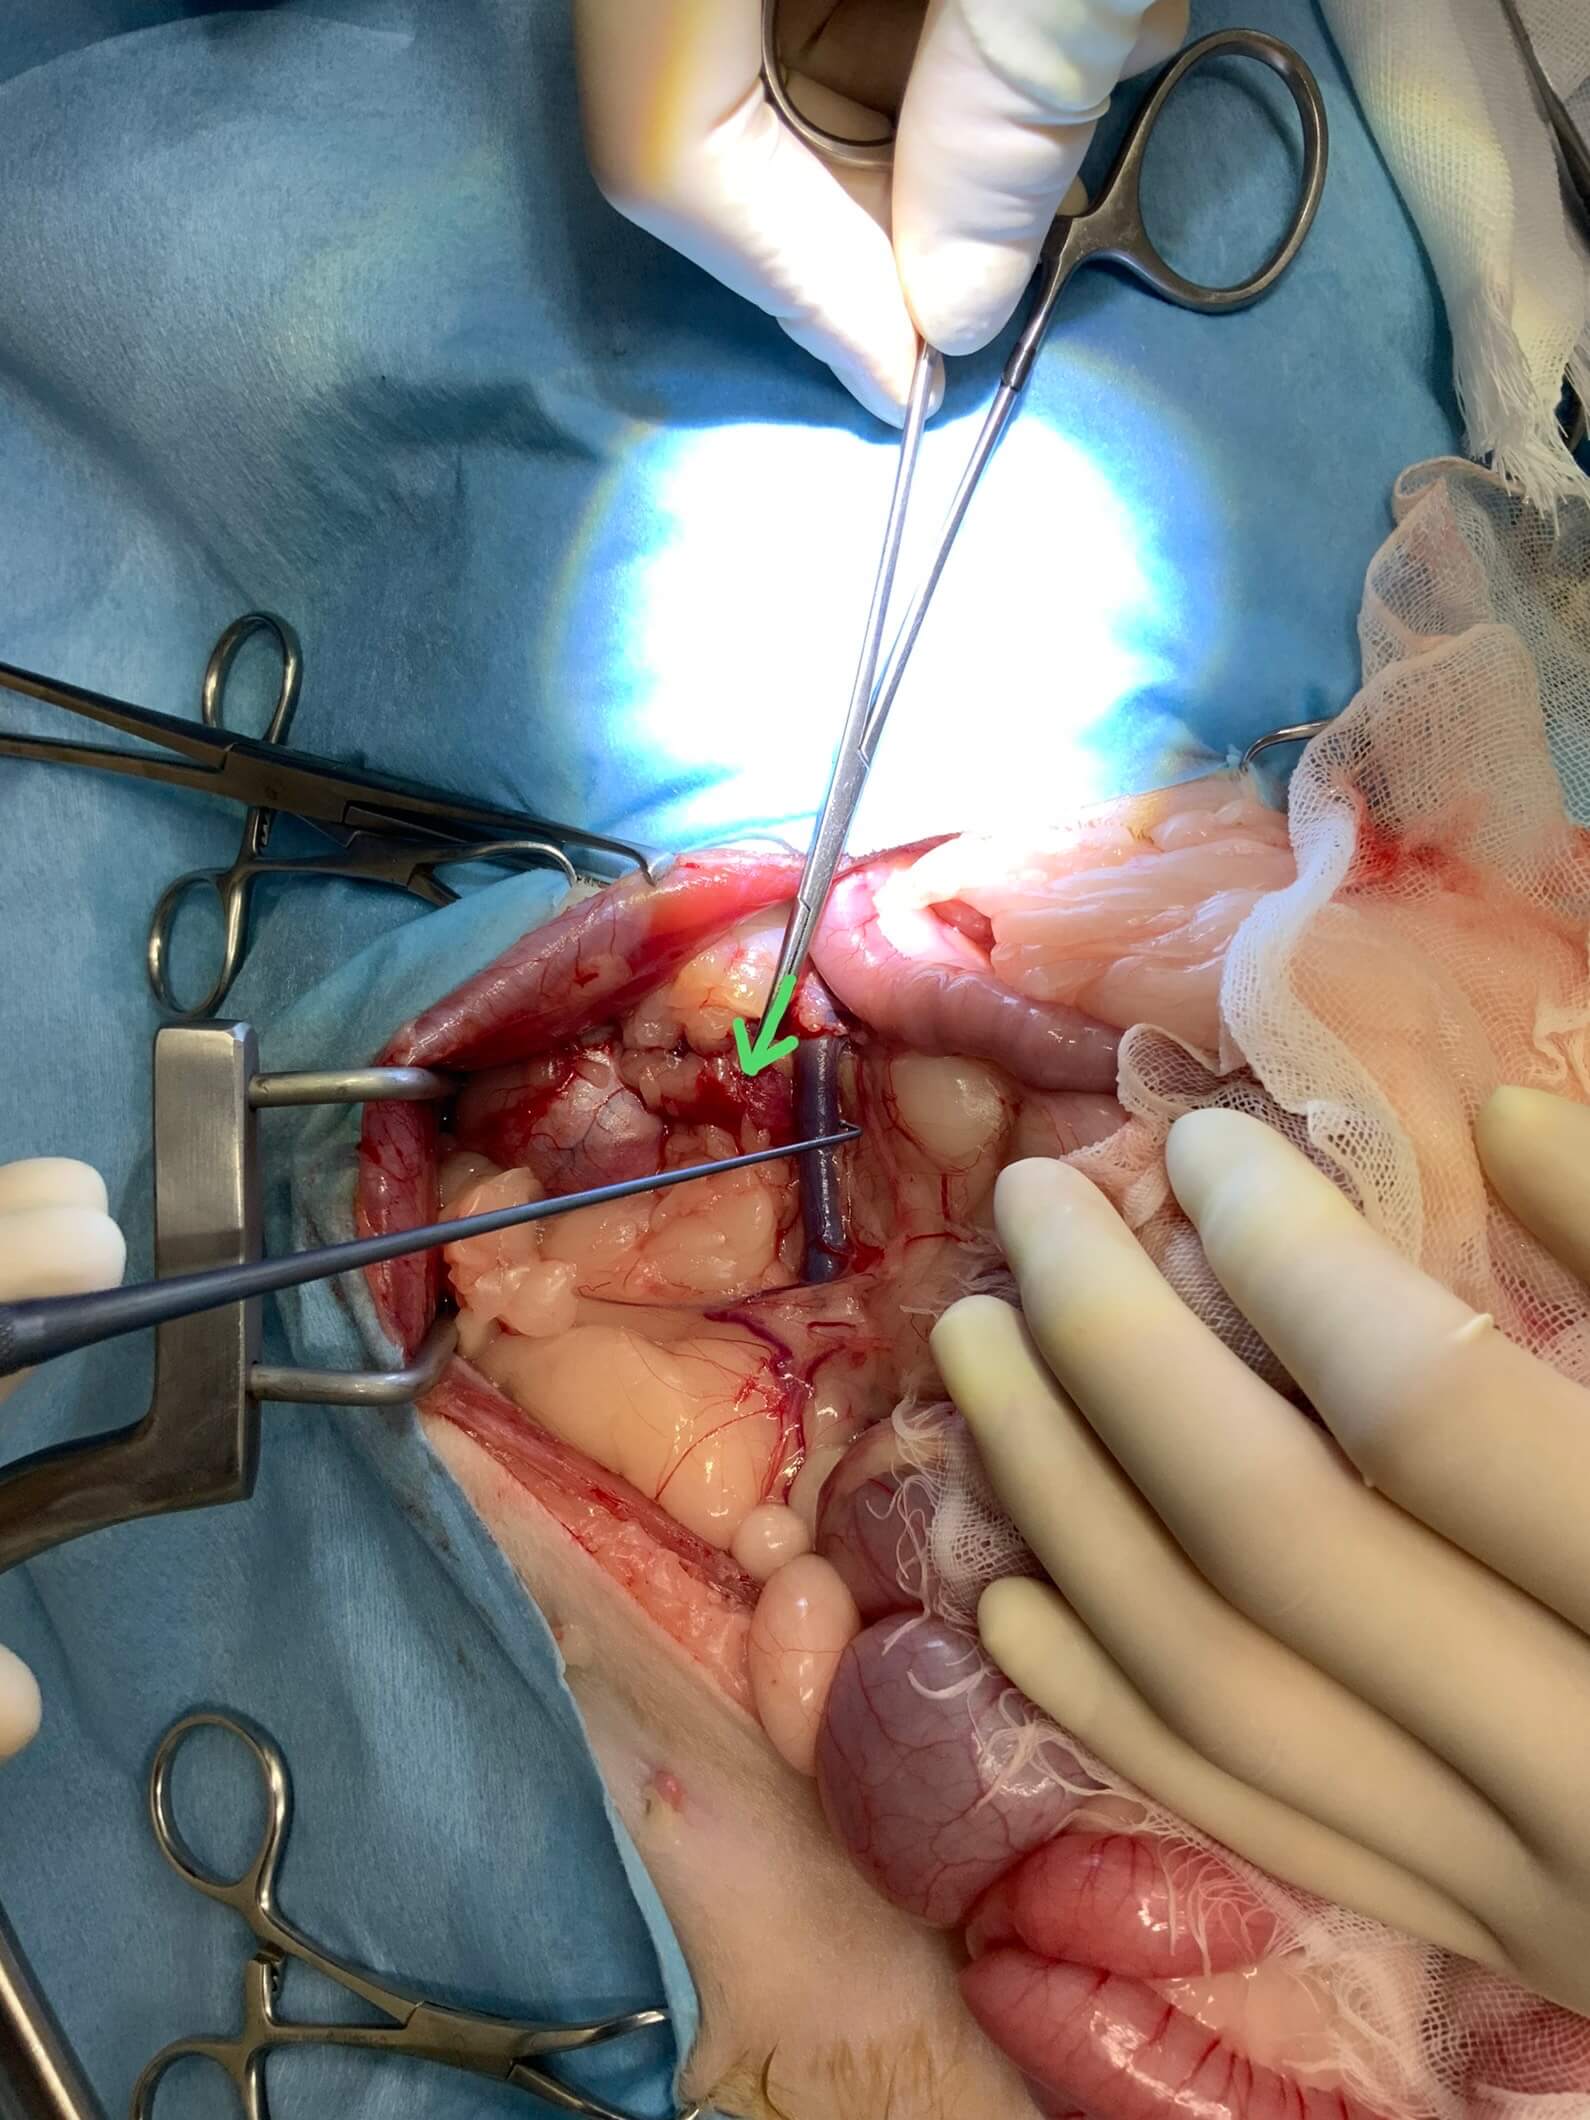

血管の背側に尿管が見えます。(矢印部)

結石が詰まっているため拡張しています。

結石を除去して 尿管を縫合しているところです。